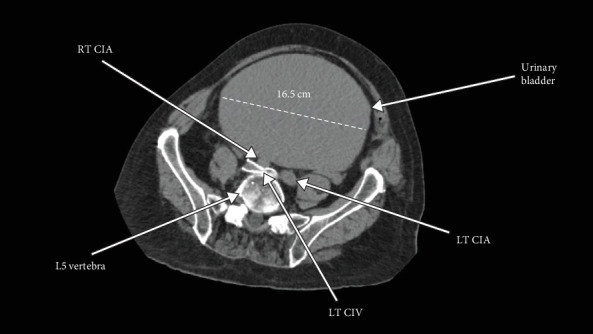

May-Thurner syndrome (MTS) is characterized by the formation of an intravenous scar or venous "spur" resulting from chronic pulsatile compression of the left common iliac vein (LCIV) by the right common iliac artery (RCIA) against the fourth or fifth lumbar vertebral body. This pulsatile compression creates a flow-limiting stenosis of the LCIV, leading to increased intravenous pressure in the veins draining the left lower extremity (LLE). Consequently, this elevated venous pressure manifests as a spectrum of chronic symptoms including unilateral LLE edema, pain, tenderness, warmth, skin inflammation, and discoloration, along with pelvic symptoms such as sensation of fullness and dyspareunia. Furthermore, MTS significantly elevates the risk of venous thromboembolism characterized by LCIV deep vein thrombosis (DVT) and potentially fatal pulmonary embolism (PE). Treatment options for MTS range from anticoagulant therapy to, in severe cases, operative intervention. Herein, we present a case of a 79-year-old male with MTS who experienced a near-fatal DVT that led to PE, compounded by a chronically distended urinary bladder, necessitating immediate operative removal of the PE.